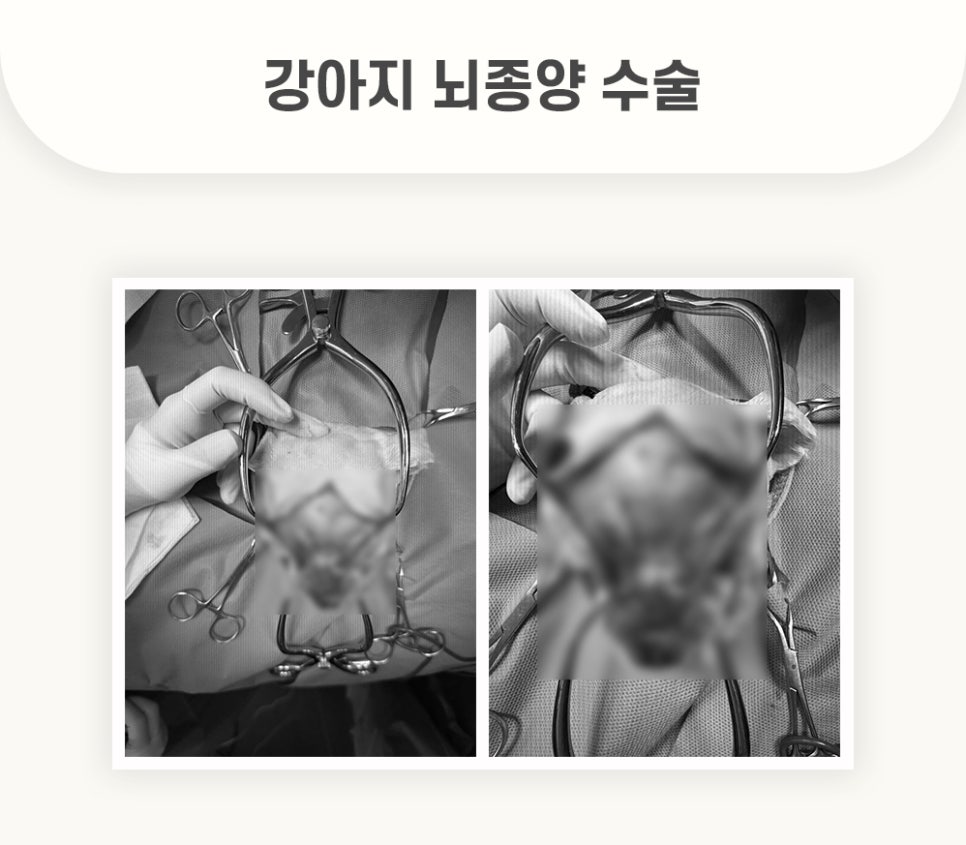

분당24시동물병원 경기동물의료원에 내원한 아* 환자는, 외과적 교정을 통한 뇌종양 수술을 진행하였습니다.

성공적으로 제거된 강아지 뇌 종양입니다. 수술 후 조직검사까지 실행하였습니다.